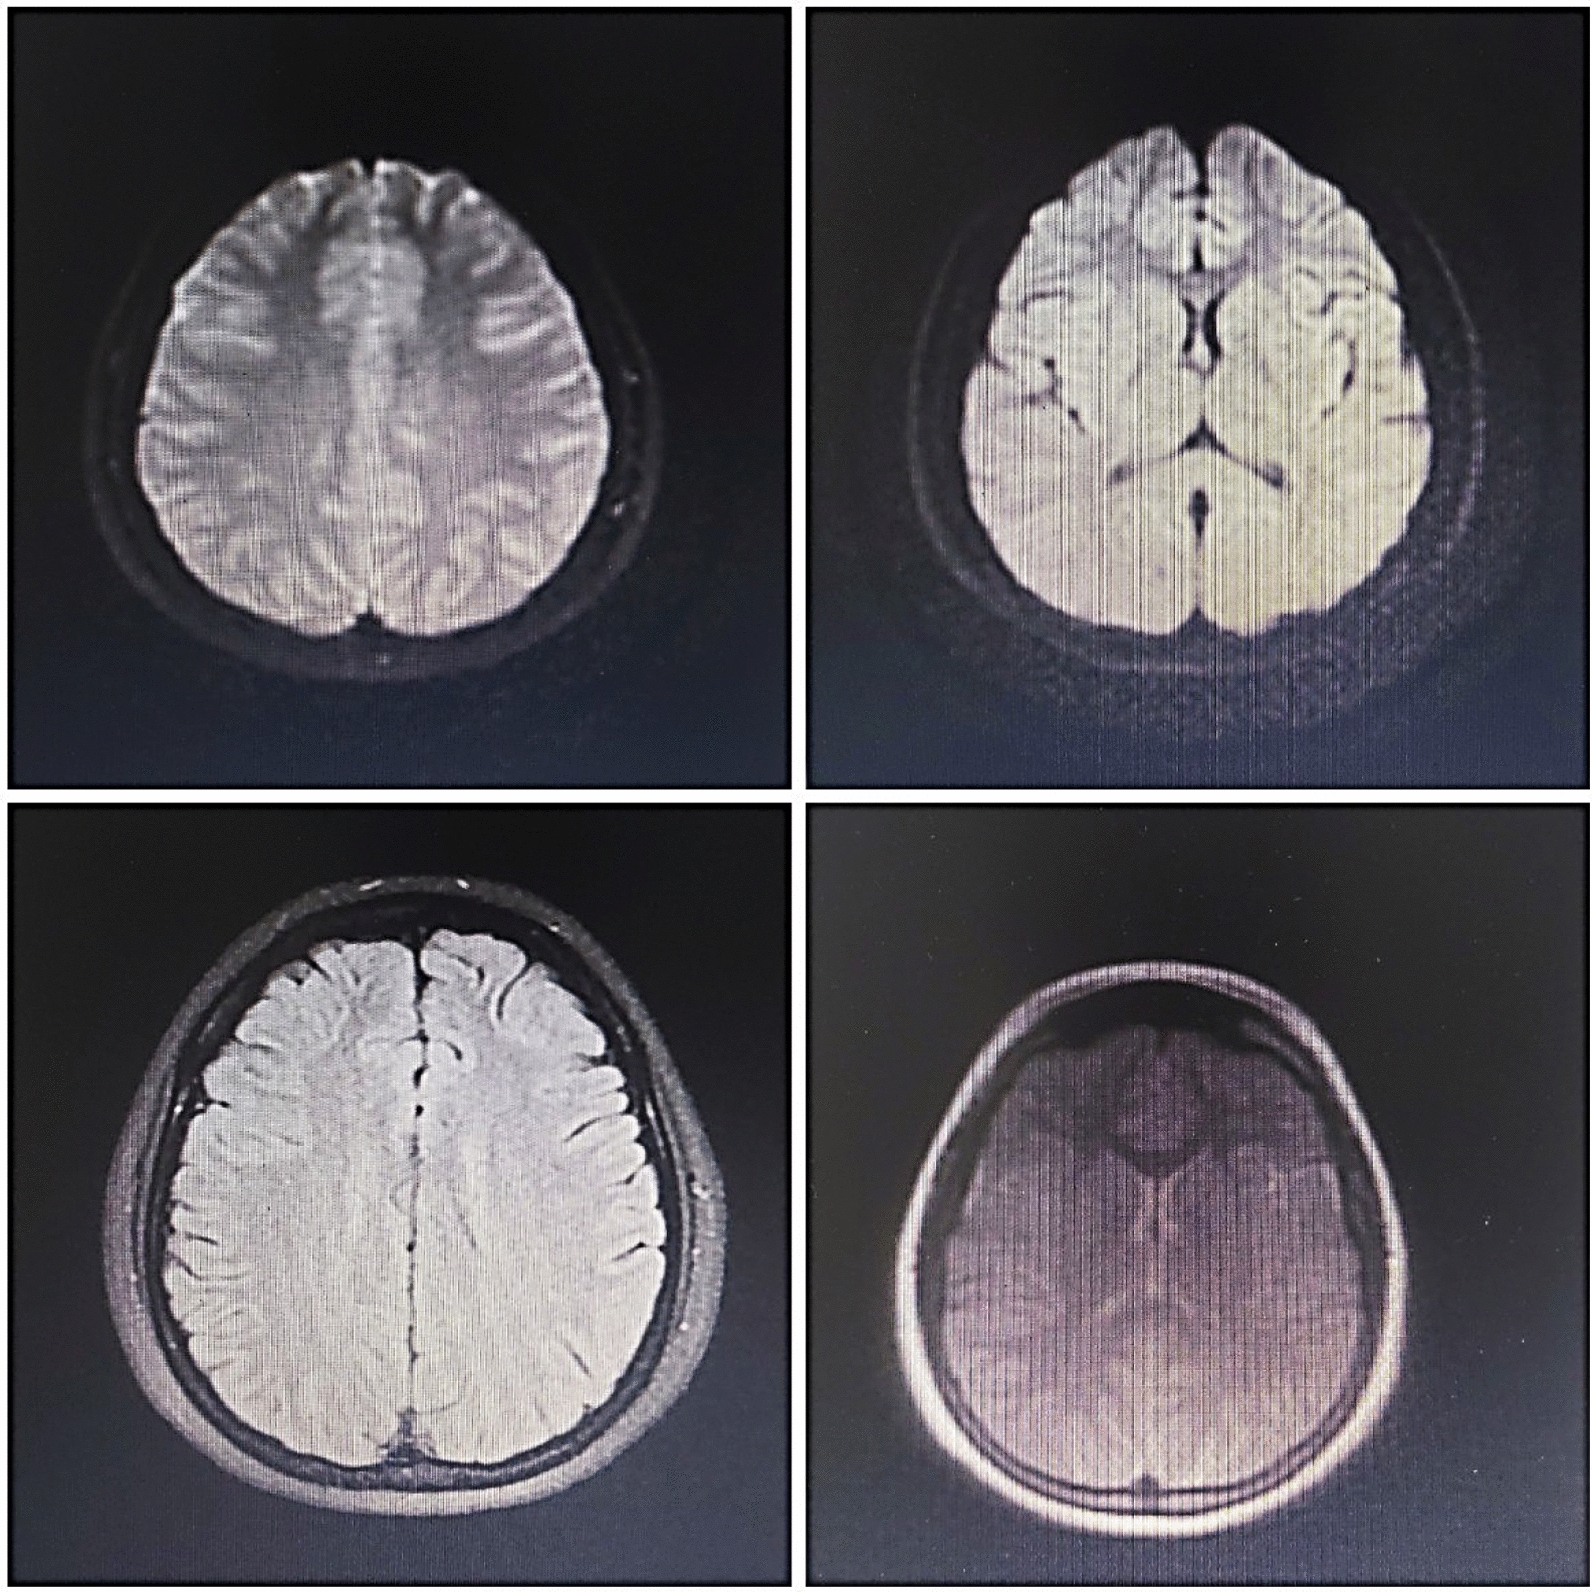

Diagnostic medical imaging

To examine the patient more closely, computed tomography (CT) scan and magnetic resonance imaging (MRI) of the brain; chest X-ray (CXR); ultrasound of the thyroid, abdomen, and pelvis; and electroencephalogram (EEG) tests were requested and performed.

In thyroid ultrasound, both thyroid lobes were normal with homogeneous parenchymal echo and without solid-cystic lesions, and no abnormal findings were seen. In the uterus and ovary ultrasound, the uterus and ovaries had normal echo and dimensions, and there was no evidence of cystic or solid lesions.

The MRI findings were normal, but several diffuse cortical hyperintensities were observed, consistent with the patient’s history of anti-NMDAR encephalitis. This may indicate an inflammatory process related to a relapse. However, the overall normal findings and the absence of abnormalities in complementary imaging studies, including brain CT, chest X-ray, and ultrasounds, suggest no concurrent structural or systemic pathology. The EEG was also evaluated and found normal (Figs. 1, 2, 3).